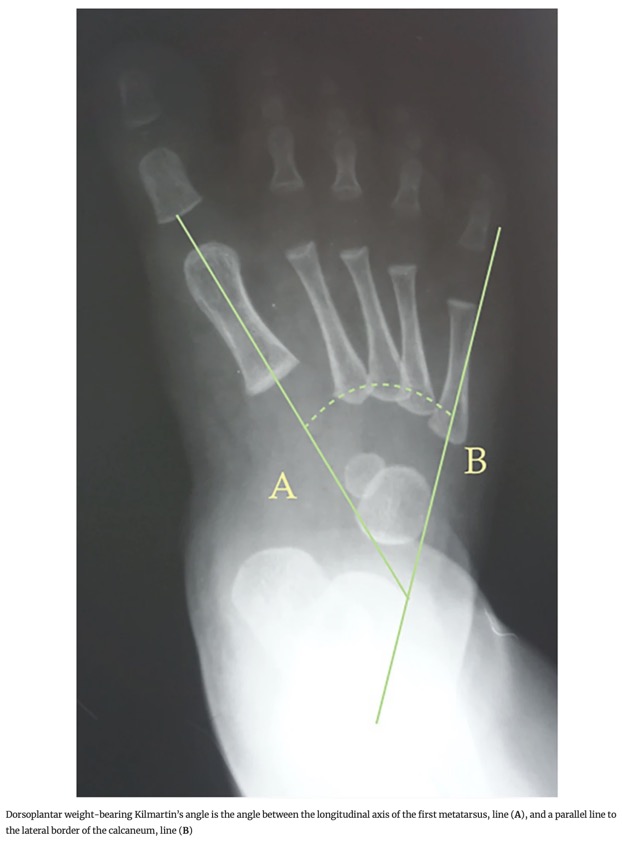

- 1. Angle de Kilmartin : Angle entre l'axe longitudinal du premier métatarsien et une ligne parallèle au bord latéral du calcaneus.